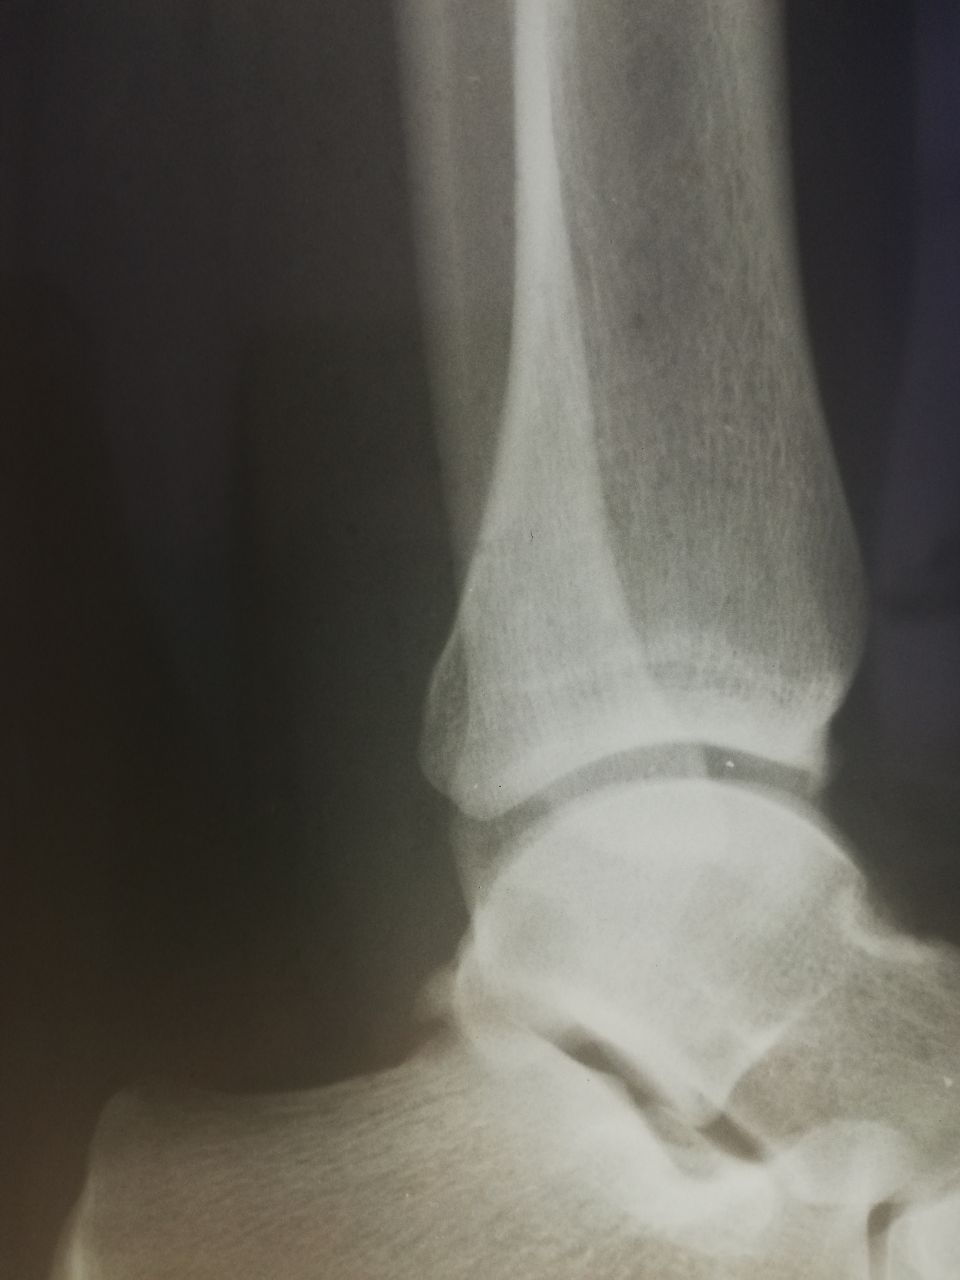

Здравствуйте! Мужчина, 37 лет, 3-4 недели назад была травма. Смущает отмеченный участок на латеральной лодыжке. Как думаете, есть ли перелом? И если есть, можно ли сказать о его консолидации?